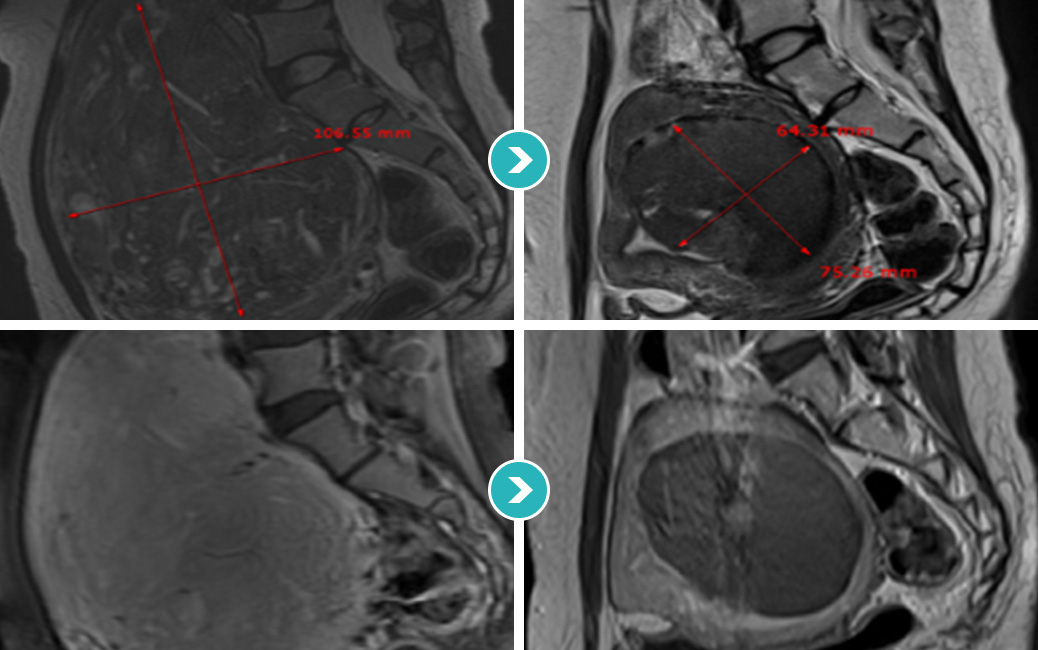

질출혈과 생리과다 및 복부에만져지는 거대 자궁근종으로 자궁근종 하이푸 치료를 위해 내원하였습니다.

하이푸 시술전 MRI사진상 척추와 복벽을 밀고있는 14cm의 혈류가 풍부한 거대 자궁근종이 관찰됩니다. 자궁근종 하이푸 치료는 자궁근종 부위만 선택적으로

치료하는 시술로 자궁근종 전체적으로 자궁근종 하이푸 치료하였고, 14cm 거대 자궁근종 하이푸 치료시간은 164분이 소요되었습니다.

(Uterine Myoma Hifu treatment time 164min)